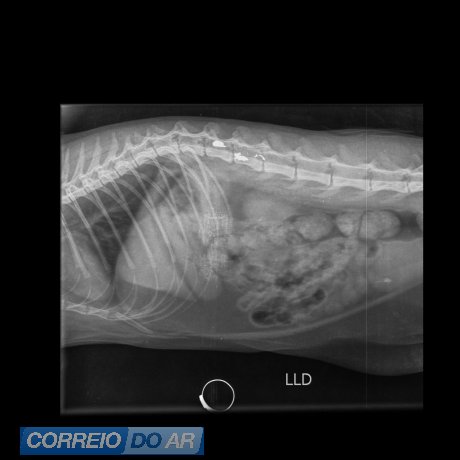

A gata foi socorrida e encaminhada para atendimento veterinário na clínica Vida Pets, onde recebeu os cuidados necessários. O animal passou por exames e procedimentos médicos após o disparo, enquanto os tutores prestaram depoimento às autoridades e acompanharam o andamento das investigações.

A gata Morgana segue internada sob cuidados veterinários e, segundo os tutores, a previsão é de que ela receba alta na próxima segunda-feira (09). Até o momento, o animal permanece em estado estável, porém ainda apresenta algumas complicações e não tem se alimentado adequadamente. A gata está sendo acompanhada de perto por profissionais da clínica e conta também com a supervisão de um médico neurocirurgião veterinário de Foz do Iguaçu-PR.